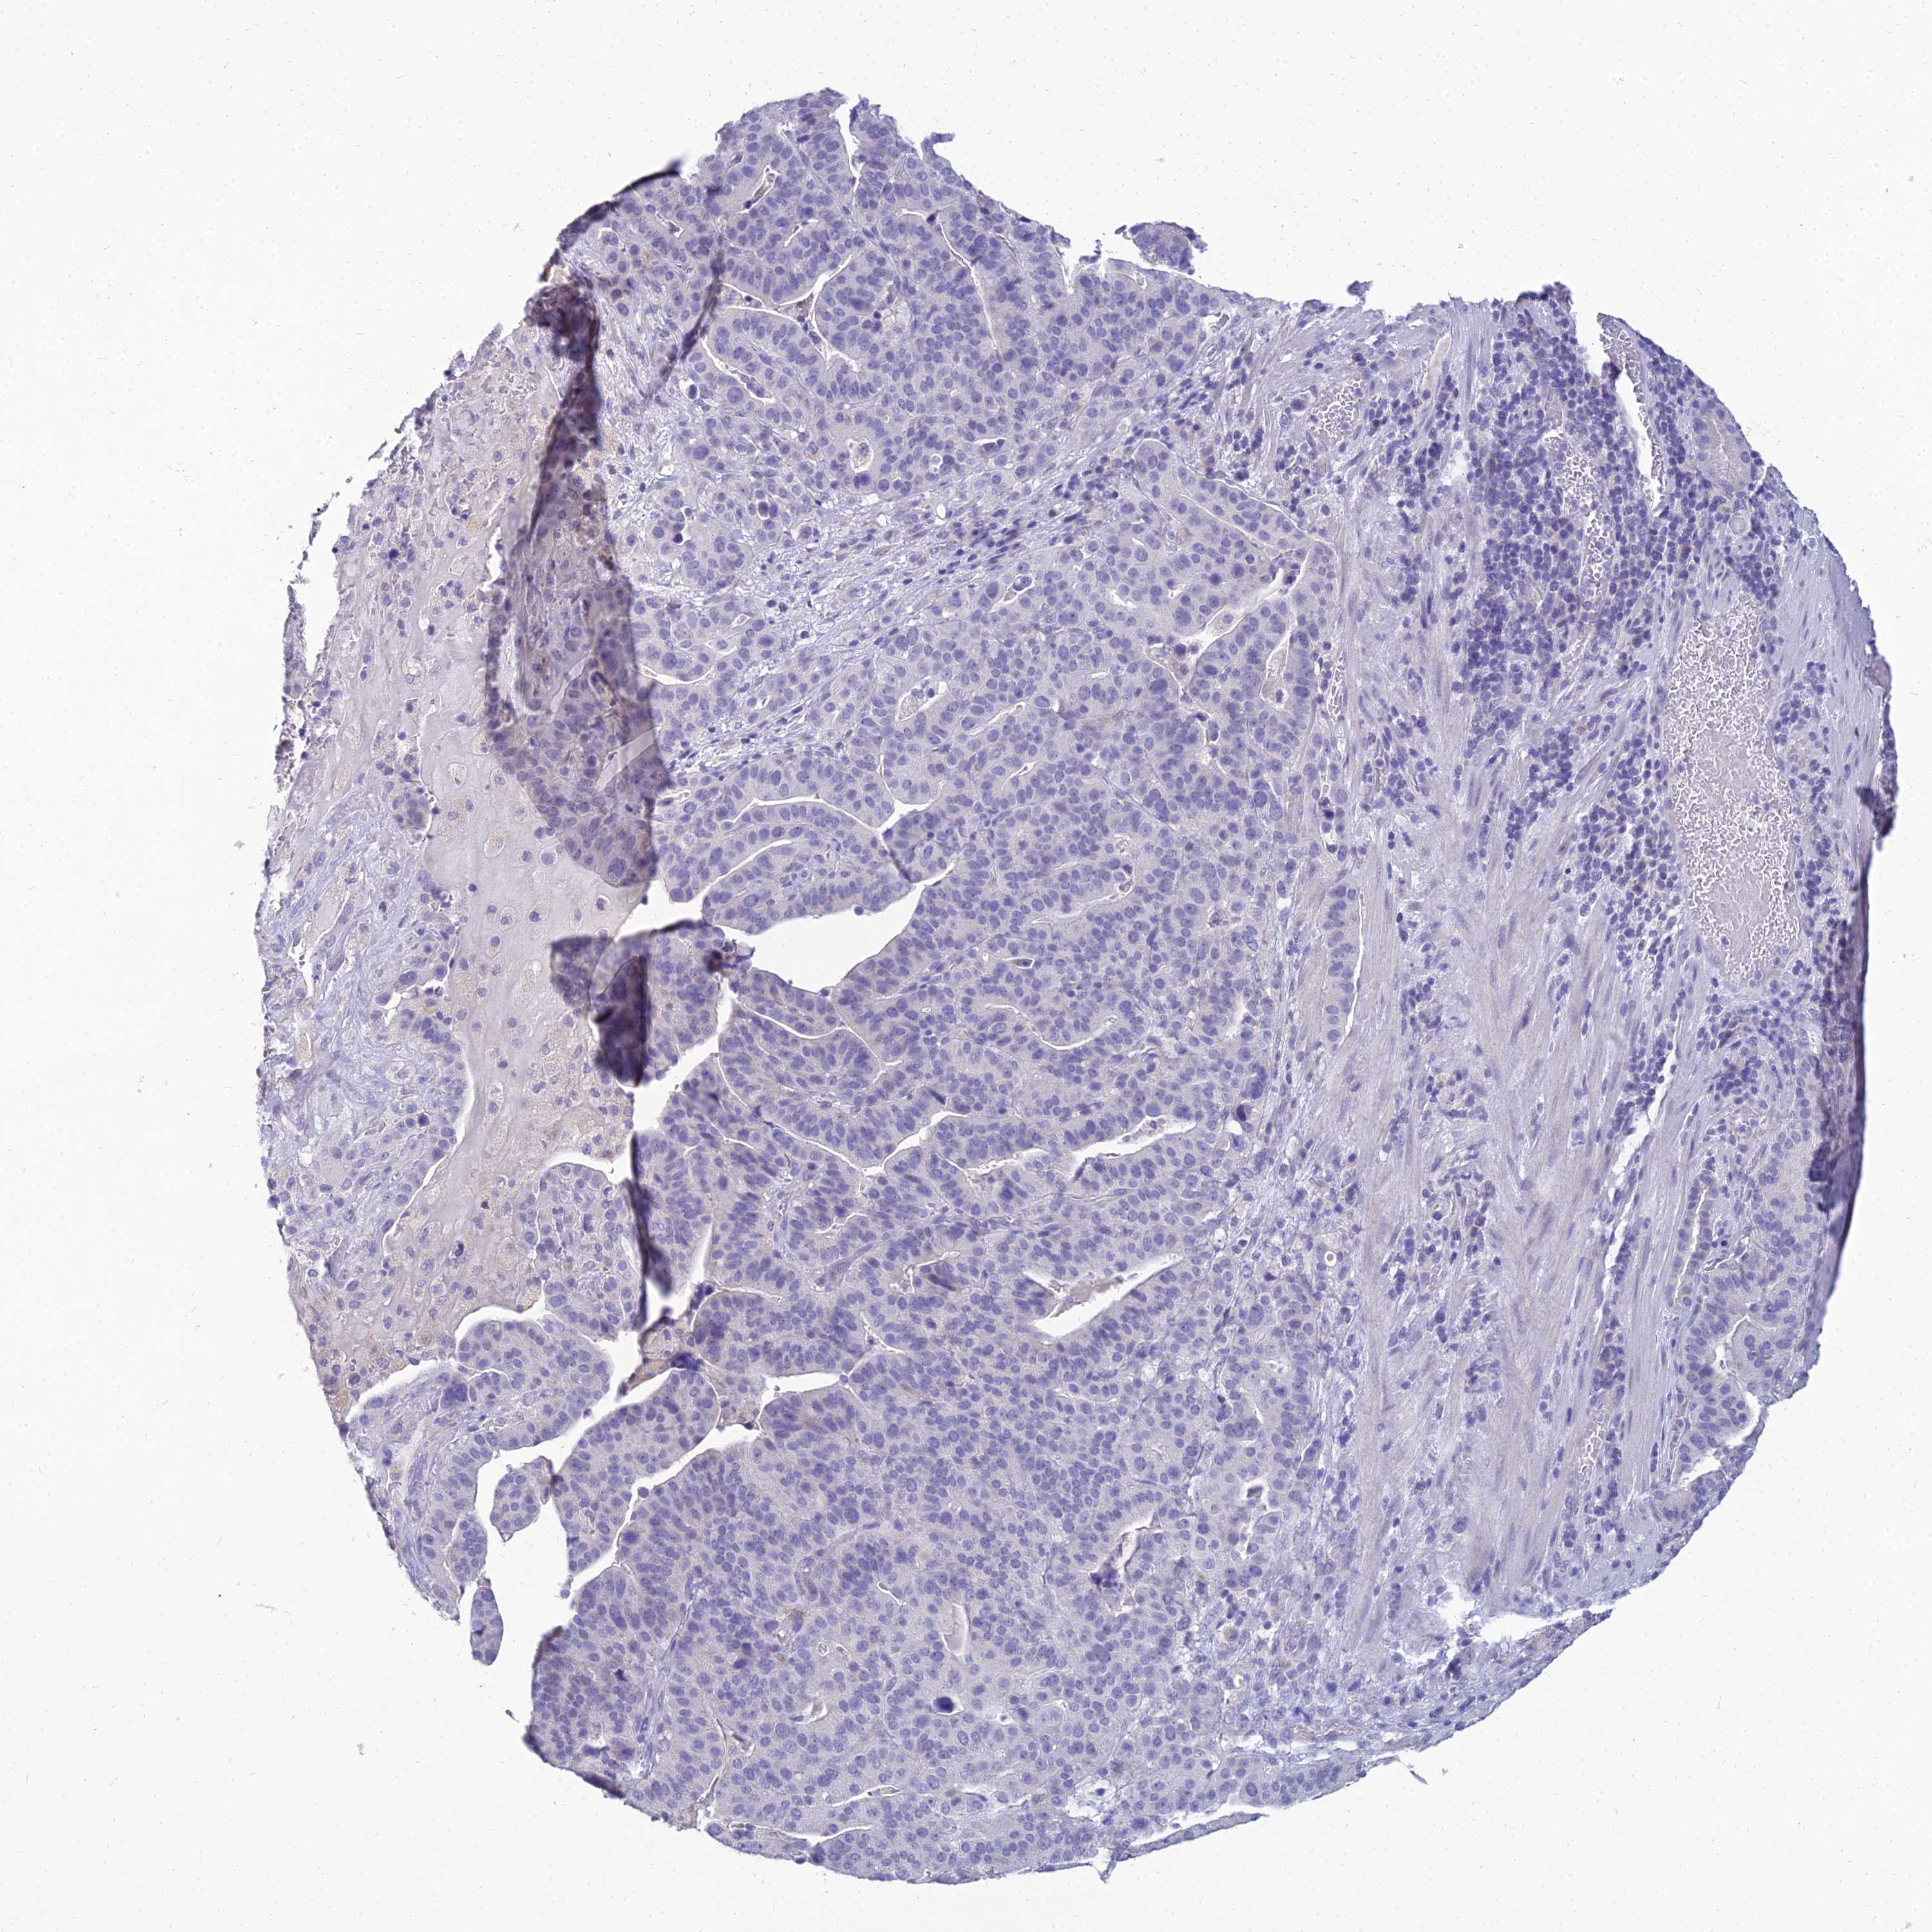

STOMACH CANCER - Protein expressioni

A mouse-over function shows sample information and annotation data. Click on an image to view it in a full screen mode. Samples can be filtered based on level of antibody staining by selecting one or several of the following categories: high, medium, low and not detected. The assay and annotation is described here.

Note that samples used for immunohistochemistry by the Human Protein Atlas do not correspond to samples in the TCGA dataset.

Antibody stainingi

Antibody staining in the annotated cell types in the current human tissue is reported as not detected, low, medium, or high, based on conventional immunohistochemistry profiling in selected tissues. This score is based on the combination of the staining intensity and fraction of stained cells.

Each image is clickable and will lead to virtual microscopy that enables deeper exploration of all samples and also displays staining intensity scores, fraction scores and subcellular localization as well as patient and tissue information for each sample.

Antibody HPA044572

Antibody HPA056798

Antibody CAB016733

Antibody CAB034368

Staining

High

Medium

Low

Not detected

Intensity

Strong

Moderate

Weak

Negative

Quantity

>75%

75%-25%

<25%

None

Location

Nuclear

Cytoplasmic/membranous

Cytoplasmic/membranous,nuclear

Adenocarcinoma, NOS